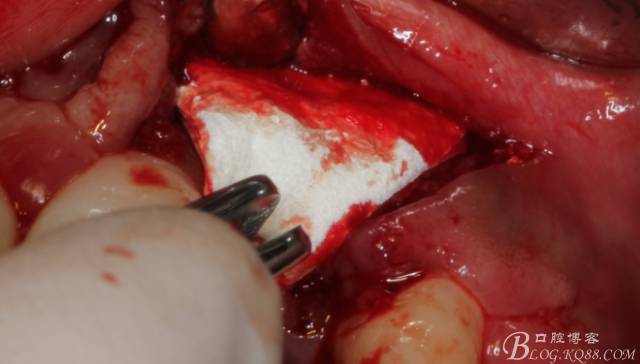

于是我果斷告知患者,手術(shù)失敗了,不能拖延,如不及時處理,炎癥繼續(xù)發(fā)展會很快波及鄰牙牙槽骨?;颊呓邮芪业慕ㄗh。切開翻瓣,骨粉及生物膜消失了,骨吸收嚴(yán)重,幸運的是,因為處理及時,鄰牙骨支持依然存在。

徹底掻刮。

有老師問我,為什么不在此時同期植骨同期植入植體?我的觀點是:不要一次做太多事情,做得越多風(fēng)險越高。再說,此時軟組織不健康,沒有健康的軟組織如何能保證GBR的成功?所以,我僅放了一塊膠原蛋白就縫上了。